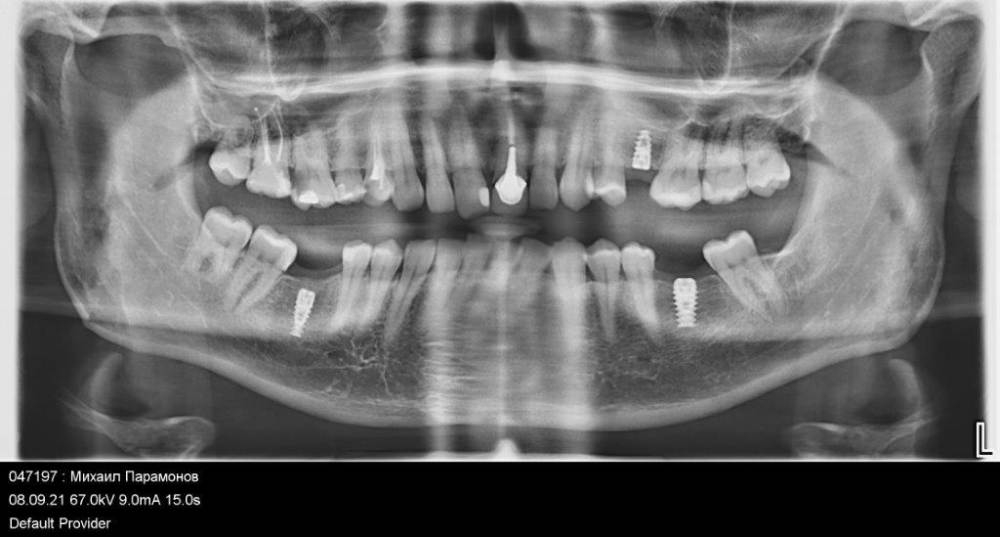

denrusof Опубликовано 10 сентября, 2021 Поделиться Опубликовано 10 сентября, 2021 Помогите пожалуйста советом что делать с 16?, терапевт предложила 3 варианта: 1. Депульпировать+ пломба 2.Депульпировать+ культя с коронкой 3. Удаление+ имплантирование Спасибо за ответы. Ссылка на комментарий

denrusof Опубликовано 12 сентября, 2021 Автор Поделиться Опубликовано 12 сентября, 2021 Сегодня депульпировали 4 канала + временная пломба, через 10 дней повторный прием на котором будет решать пломба или коронка Ссылка на комментарий